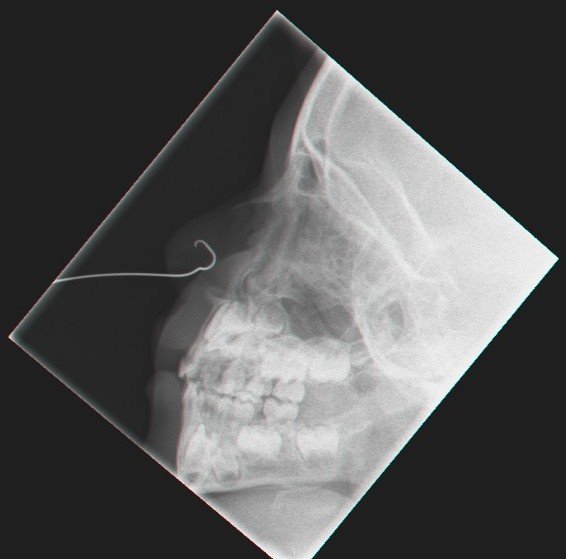

נועם עמר (3.5), תושב יבנה, הגיע בסוף השבוע עם אמבולנס לחדר מיון ילדים בית החולים קפלן כשצינורית מתכת ברוחב 18 ס"מ התעקלה בחלקה בתוך מחיצת האף.זאת, לאחר שהחדירה בטעות לאפו והוריו לא הצליחו לשלוף אותה בשל מיקומה בתוך האף. רופאי מחלקת אף, אוזן וגרון הצליחו לשלוף את הצינורית בהצלחה לאחר צילום הדמיה תוך מניעת פגיעה בחלל האף.

ד"ר גיל צויזנר, רופא אף אוזן וגרון בבית החולים קפלן, אמר כי הפעוט הגיע לחדר המיון כאשר קצה צינורית מתכת תקוע בתוך מחיצת האף. "ערכנו באופן מידי בדיקה מקיפה, כולל צילומי הדמיה, בכדי לבדוק היתכנות דימומים או פגיעה באזורי הנשימה, העיניים והמוח. לשמחתנו, לא נראתה פגיעה באזורים אלו". בדיקת ההדמיה סייעה בידי הרופאים לשלוף את הצינורית שהתעקלה במחיצת האף בהצלחה וללא דימומים. לאחר שהצינורית נשלפה נשאר הפעוט להמשך השגחה ולאחר מכן נשלח לביתו.